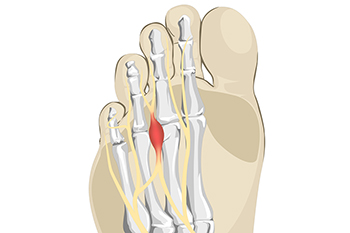

Stretches That May Help the Pain of Morton’s Neuroma

Stretches That May Help the Pain of Morton’s NeuromaThe foot condition that is known as Morton’s neuroma affects the nerve between the third and fourth toes. In severe cases, it is quite painful. This can possibly be treated without surgery in the beginning stages. It...